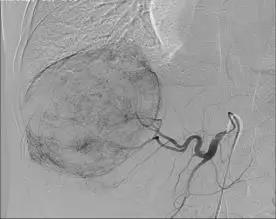

60歲的劉大爺5個月前右上腹部出現(xiàn)疼痛,在當?shù)蒯t(yī)院檢查確診為晚期巨大肝癌,去其他醫(yī)院檢查后仍然是同樣的結(jié)果,醫(yī)生說已經(jīng)沒有治療的價值,建議他回家好好享受剩下的日子。就在他絕望的時候,同村的人向他介紹說我院普外科對待病人“肝膽相照”。劉大爺抱著試試看的心態(tài)住進我院普外科,經(jīng)過詳細檢查發(fā)現(xiàn),右肝巨大腫物約為12×11×11厘米且伴仔瘤,肝硬化,左半肝變小,確診為原發(fā)性晚期巨大肝癌。

栓塞術(shù)中顯示的肝部腫瘤與栓塞術(shù)后CT顯示的腫瘤對比

“這種情況不宜切除右半肝臟,因為左半肝體積小,余肝不能代償,切除后會導致肝功能衰竭,危及生命。必須先行介入治療,把供應肝臟腫瘤的血管堵死,‘餓死’癌細胞,使癌瘤縮小,左肝代償增大,待肝癌降期后再行手術(shù)治療,效果會比較好,也比較安全。”濰坊市市立醫(yī)院普外科主任醫(yī)師遲景濤分析說。

劉大爺住院期間共經(jīng)過“經(jīng)皮經(jīng)股動脈穿刺肝動脈選擇性造影并肝癌灌注化療栓塞術(shù)”介入治療兩次,巨大肝癌明顯減小,普外專家團隊擇期為其進行了手術(shù),而且又成功實施了肝第Ⅶ段、第Ⅵ段切除手術(shù)。劉大爺康復出院時精神抖擻,滿面笑容,還滿意的說癌癥再厲害也敵不過濰坊市市立醫(yī)院普外科專家的手術(shù)刀!